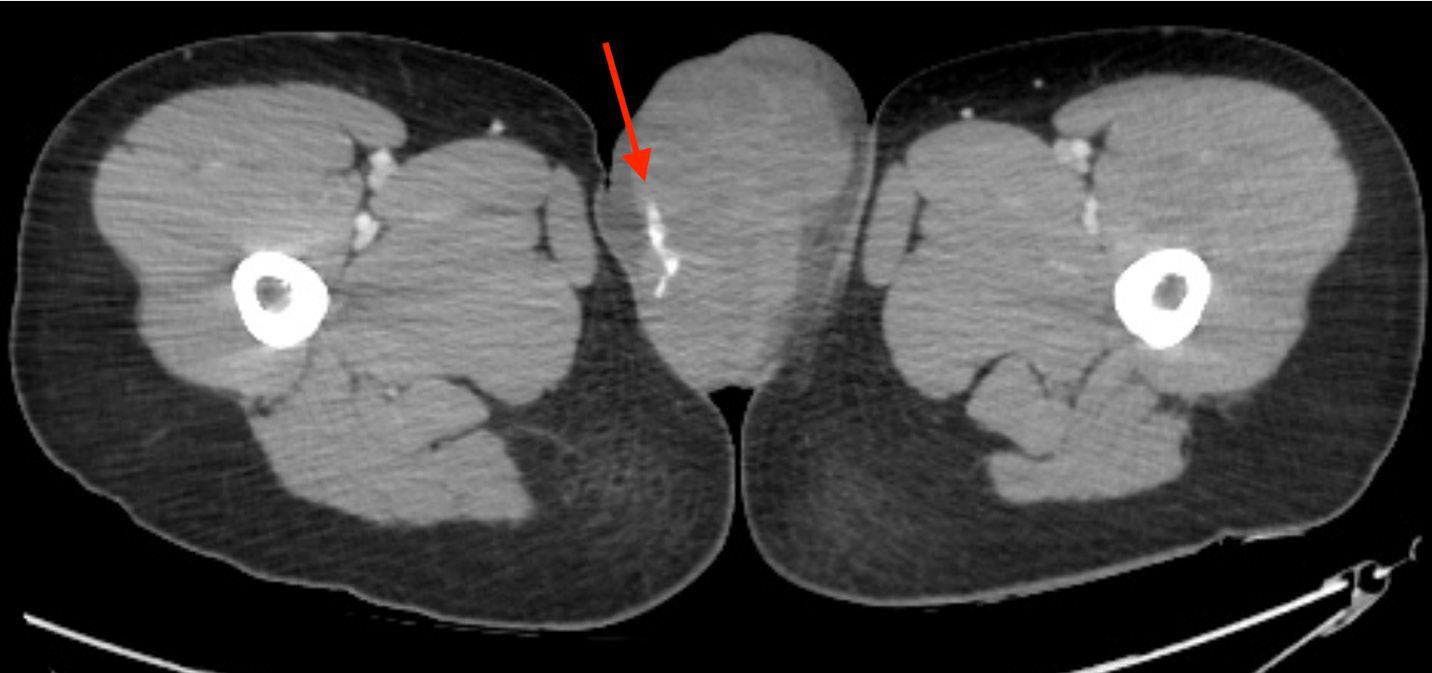

294 Presentation of Renal Cell Carcinoma Invading into the Pulmonary Artery in the Emergency Department: Case Report

S Yang, C Jewell